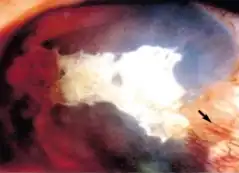

| Pseudopterygium is seen arrow (and calcified plaque) | |

Pseudopterygium is the conjunctival adhesion to cornea caused by limbal or corneal inflammation or trauma. The pseudopterygium can be easily distinguished from pterygium by bowman's probe test.[1] Because of the lack of adherence of pseudopterygium at every point, the probe can be passed beneath it at some point.